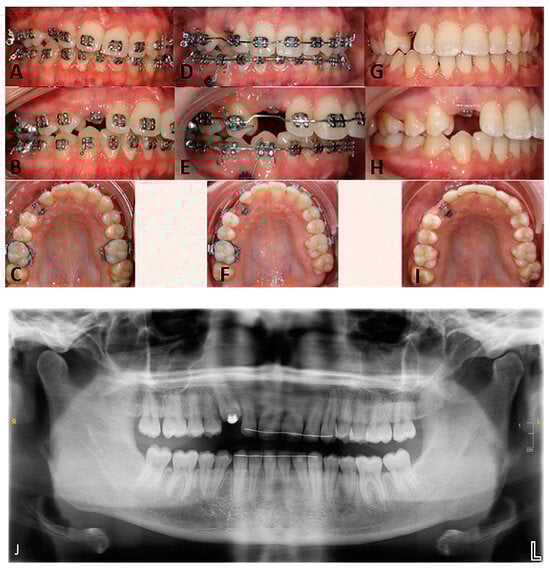

Figure 3. Frontal intraoral views in occlusion, right lateral views, occlusal views of the maxillary arch: (AC)—initial situation, at the first consultation; (DF)—intermediate situation, during the second orthodontic treatment; (GI)—clinical situation upon debonding, (J)—post-treatment orthopantomogram.

Upon clinical and radiological examination (Figure 1, Figure 2 and Figure 3), the patient exhibited a harmonious face; a reduced lower facial height; an impacted, ankylosed, and severely infra-occluded right maxillary canine; an upper dental midline deviated 2 mm to the right; a skeletal class II associated with a class II division 1 malocclusion; and an iatrogenic clockwise cant of the maxillary occlusal plane with simultaneous adaptation of the mandibular arch. Several root resorptions were observed, with all maxillary incisors exhibiting signs of this phenomenon. However, the central incisors appeared to have undergone a particularly pronounced degree of root resorption. The clinical diagnosis of ankylosis of # 13 (upper left canine, World Dental Federation notation) was confirmed by the observation of a cant of the occlusal plane, a metallic sound after axial percussion, and a lack of mobility of the canine. A radiographic examination (Figure 2) revealed that the root was centred within the alveolar process. An external resorption with bone replacement was evident in the cervical region on the buccal side of the canine, indicative of tooth ankylosis. In contrast to the thicker palatal cortical bone, the buccal cortical plate was less than one millimetre thick.

The initial correction of the iatrogenic occlusal plane cant was conducted through orthodontic means, utilising a mandibular temporary anchorage device (TAD) and the ankylosed canine as anchorage points, with the application of extrusion and intrusion mechanics (Aarhus miniscrew, American Orthodontics, Sheboygan, WI, USA; Victory Series brackets, 3M, Saint Paul, MN, USA). The sagittal component of the malocclusion was not addressed in order to reduce the overall treatment time and to avoid exacerbating the existing root resorptions (Figure 3).